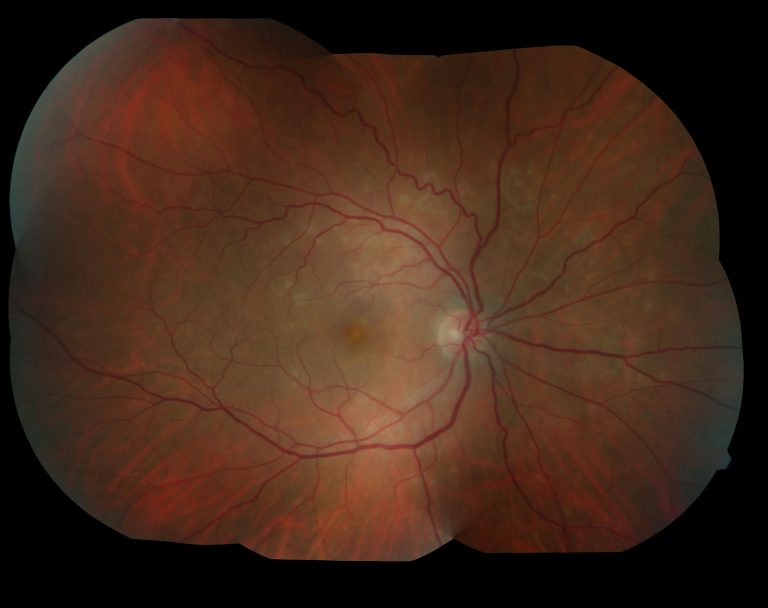

In addition, her eye tissue was torn, optic nerves were swollen, and multiple pale-coloured lesions were scattered throughout the back of her eye.